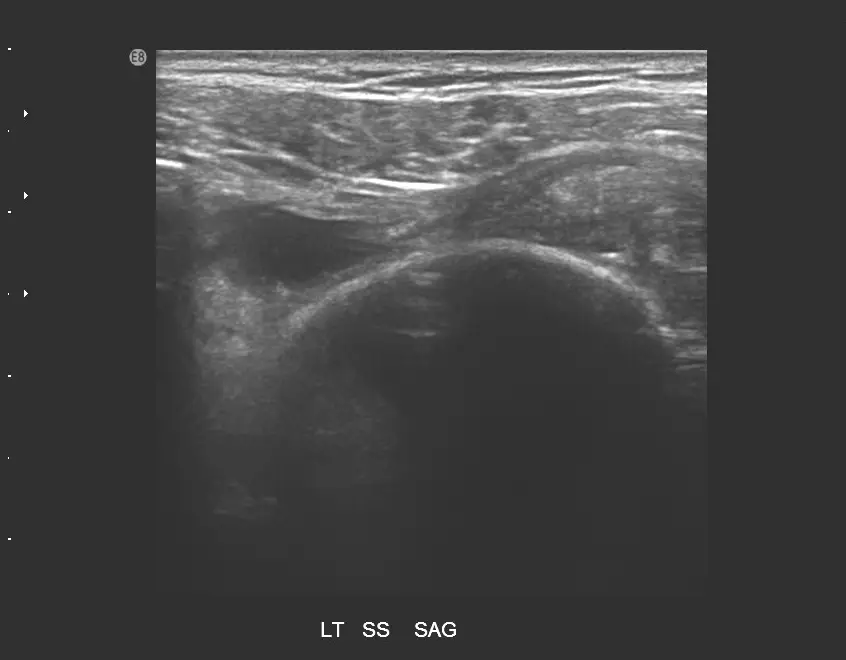

85 歲女性患者,主訴左肩疼痛超過 6個月,有局部壓痛,無肌肉萎縮現象,圖為左肩部超音波檢查,上圖為旋轉環帶長軸切面,下圖為短軸切面,最可能之診斷為何?

上圖(長軸切面,LT SS SAG): 左肩棘上肌腱矢狀面(長軸)超音波影像。正常棘上肌腱在長軸切面應呈現纖維狀(fibrillar)排列的高回音帶狀結構,覆蓋於肱骨頭(humeral head)弧形高回音骨皮質上方。本圖可見:

- 棘上肌腱區域出現明顯低回音/無回音缺損(hypoechoic/anechoic defect),正常纖維狀肌腱回音結構消失

- 三角肌(deltoid muscle)向下陷入缺損處(deltoid dipping sign),為全層斷裂的特徵性表現

- 肱骨頭骨皮質直接暴露於缺損下方,無正常肌腱覆蓋

- 整體表現符合棘上肌腱全層斷裂(full-thickness tear)